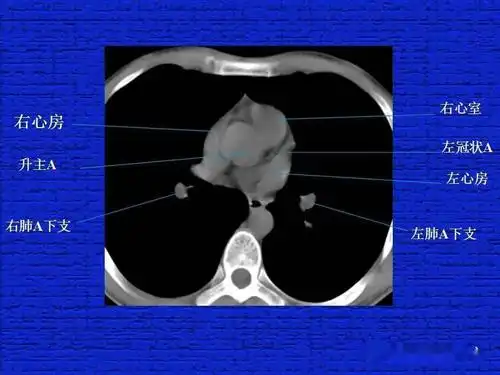

结合解剖谈正常胸部ct读片